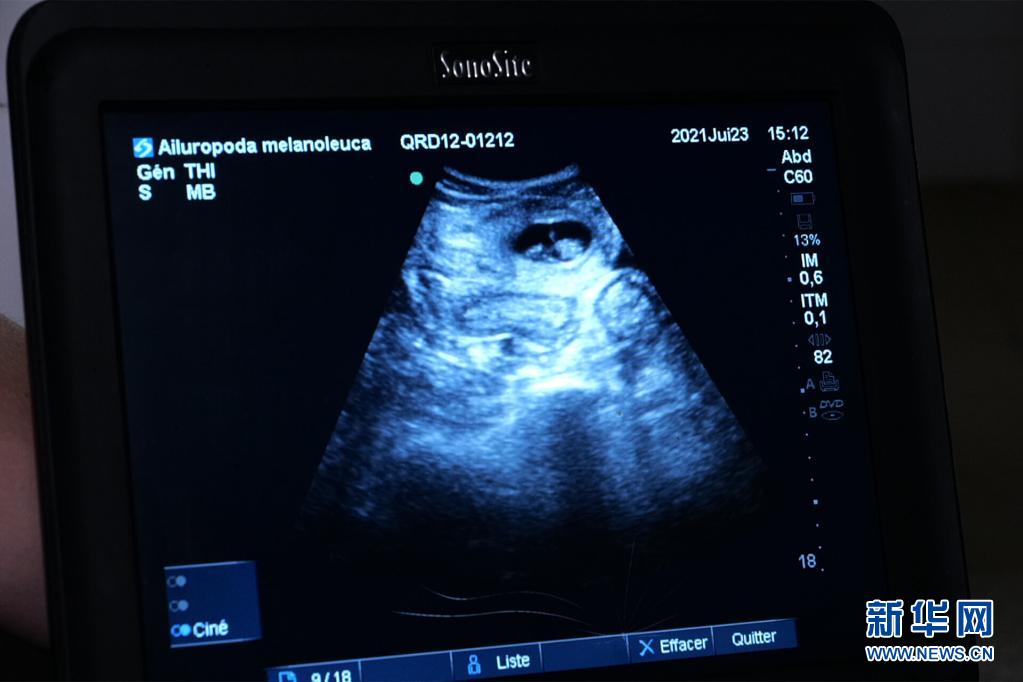

这是7月23日在法国中部圣艾尼昂市博瓦勒野生动物园拍摄的大熊猫“欢欢”的超声波检查照片。新华社发(博瓦勒野生动物园供图)

博瓦勒野生动物园当天发表新闻公报说,继20日发现“欢欢”腹中首个胚胎后,动物园兽医23日在为“欢欢”做超声波检查时,在其子宫另一侧发现第二个胚胎。

博瓦勒野生动物园发言人20日曾宣布,此前对“欢欢”的超声波检查证实其腹中存在胚胎。荷尔蒙分析结果显示,预产期应该在7月底或8月初。兽医团队接下来每周将对“欢欢”进行两次超声波检查。